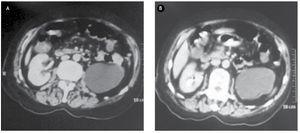

Para completar el protocolo diagnóstico se solicitó urotomografía, en la cual se puede observar el mismo defecto de llenado en polo superior del riñón derecho con 46 UH y de aproximadamente 22 mm, y una bolsa hidronefrótica del lado izquierdo (Figura 3).

Figura 3. A) y B) Urotomografía. Evidenciando bolsa hidronefrótica del lado izquierdo y tumor urotelial en cáliz superior de aproximadamente 22 mm.